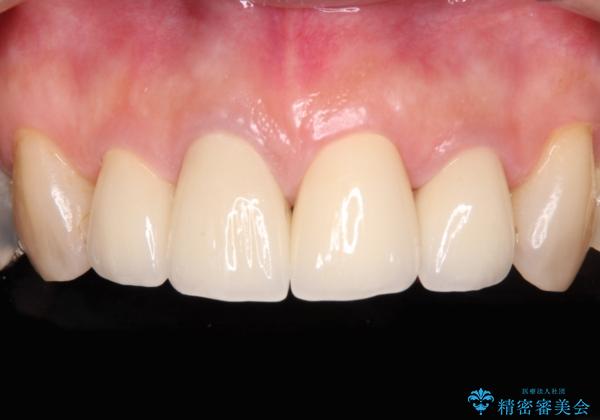

前歯は神経を取り除いて変色した歯や金属の縁が見える歯などがあり審美的に気になっていましたが、治療するかどうかは悩んでいらっしゃいました。

ところが、奥歯の治療を開始する前に、神経が失活して根尖部に病変のある前歯が著しく痛み出したため、根管治療を行うこととなりました。

奥歯の治療をしている間に前歯の治療をどのように勧めるのか検討していただき、最終的には4歯を一度に治療し、審美的に仕上げることとしました。